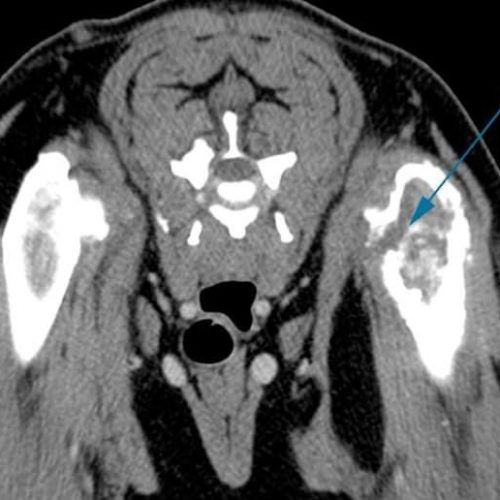

TC MULTISTRATO